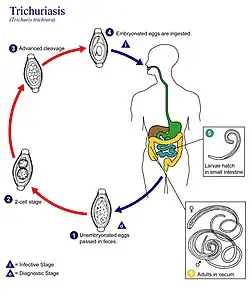

| Life cycle of Trichuris trichiura | |

Life cycle

Unembryonated eggs (unsegmented) are passed in the feces of a previous host to the soil. In the soil, these eggs develop into a 2-cell stage (segmented egg) and then into an advanced cleavage stage. Once at this stage, the eggs embryonate and then become infective, a process that occurs in about 15 to 30 days). Next, the infective eggs are ingested by way of soil-contaminated hands or food and hatch inside the small intestine, releasing larvae into the gastrointestinal tract. These larvae burrow into a villus and develop into adults (over 2–3 days). They then migrate into the cecum and ascending colon where they thread their anterior portion (whip-like end) into the tissue mucosa and reside permanently for their year-long lifespan. About 60 to 70 days after infection, female adults begin to release unfertilized eggs (oviposit) into the cecum at a rate of 3,000 to 20,000 eggs per day, linking the life cycle to the start.

- The exact incubation period of T. trichiura is unknown, however, immature eggs in soil under favorable conditions take about three weeks to mature: 15–30 days, 10 days minimum to mature before ideal ingestion by the human host. Favorable conditions for maturation of eggs are warm to temperate climates with adequate humidity or precipitation, as ova are resistant to cold, but not resistant to drying.

- Once ingested, the larva will remain dug into a villus in the small intestine for about 2–3 days until it is fully developed for migration to the ileocecal section of the gastrointestinal tract.

- The average total life span of T. trichiura is one year, although there have been longer cases reported, lasting as long as five years (Note: inadequate treatment and re-infection are likely to play a role in this).